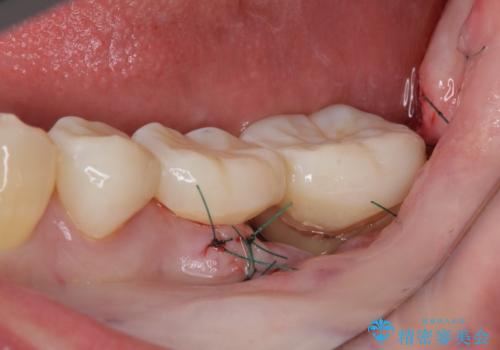

根管治療を行うためにブリッジを除去したところ、むし歯が歯肉の奥深くにあまで及んでいたため、歯周外科処置によりむし歯が歯肉縁より浅い位置へと改善することとしました。

ここまでの治療を提案したところで、折角なのでしっかり治療を行いたいとのことで、前歯のデコボコやクロスバイトを改善するための矯正治療を行うこととしました。

まずは奥歯の痛みを改善し、その後矯正治療を行い、最後にオールセラミックブリッジによる補綴治療を行うこととしました。